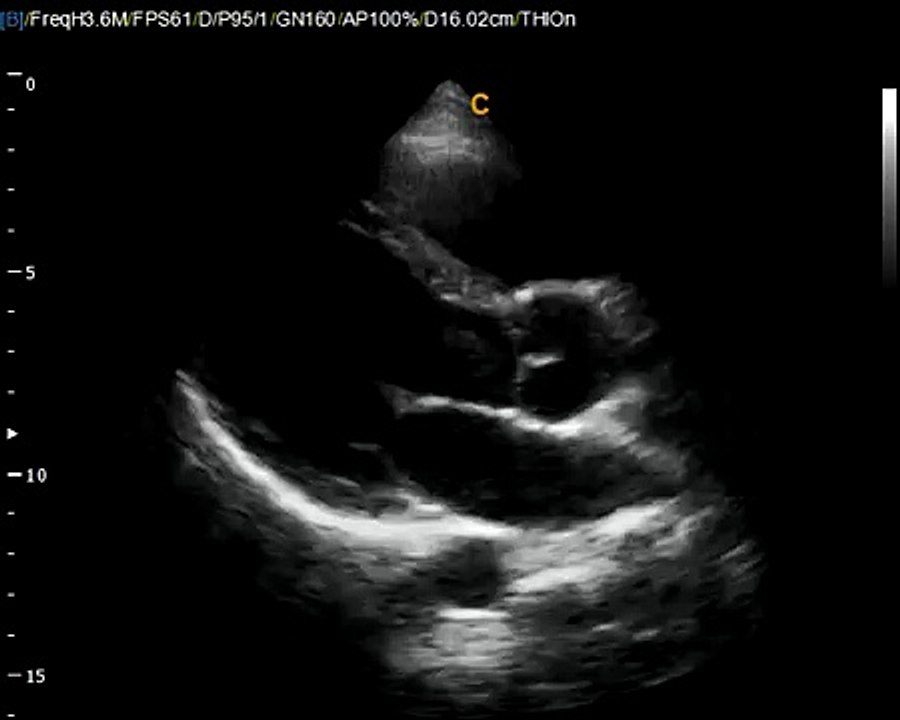

CASIS: CArdiac Simulation & Imaging Software, Quetigny

Cet été, partez à la découverte des entreprises innovantes en Bourgogne-Franche-Comté, c'est Made In Bourgogne Franche Comté!<br /><br />Découvrez CASIS: CArdiac Simulation & Imaging Software, Quetigny <br /><br />Made In Franche Comté, le dossier complet, c'est ICI ➡https://bit.ly/2HGUek2